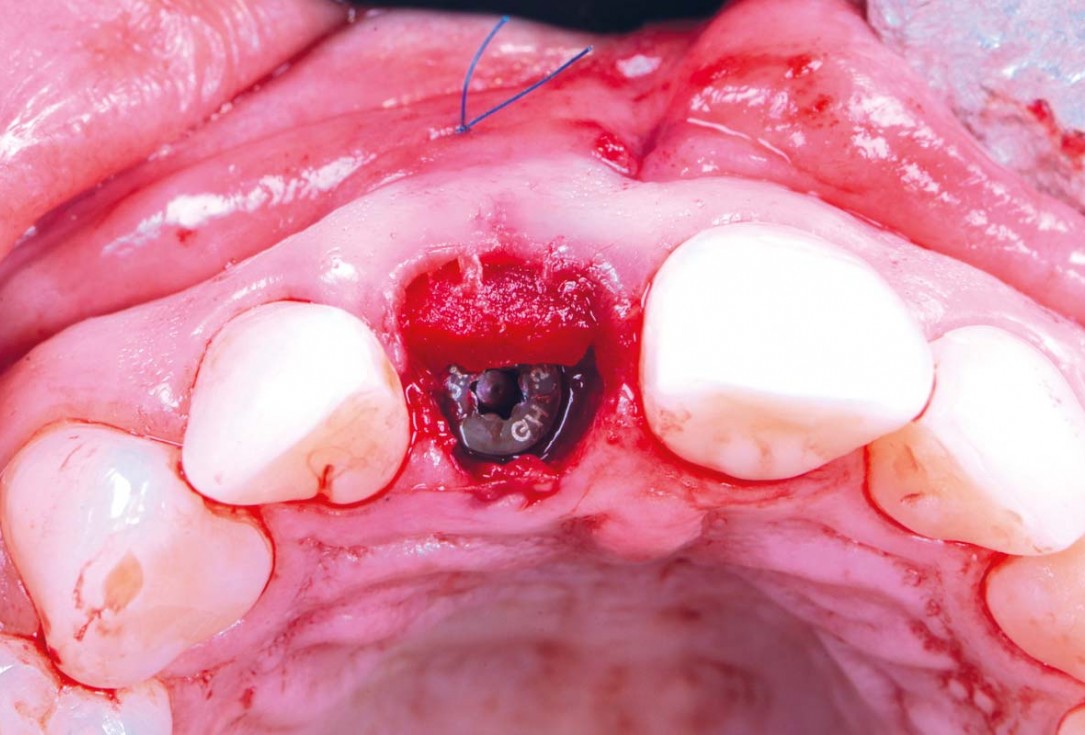

11/30 - Bone profiler was used to remove supracrestal boneExcellent aesthetic result of buccal augmentation with mucoderm® and maxgraft® after immediate implant placement - 3-years follow-up - Dr. A. Puišys